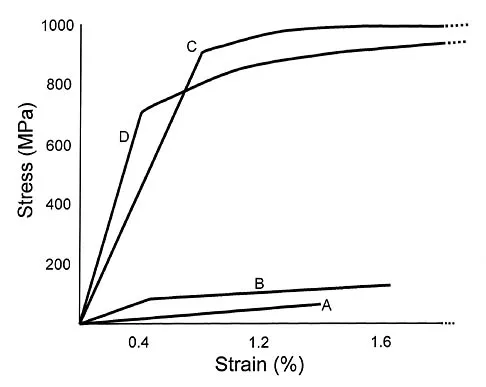

Design factors that enhance the long-term survival of proximally coated cementless hip implants include both initial stability and

Explanation